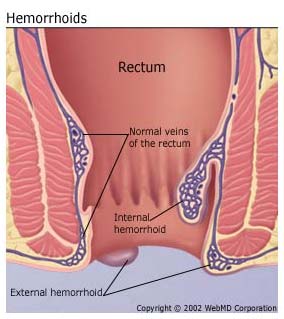

هموروئید عبارت است از بالشتک های عروقی طبیعی در کانال مقعد که به کنترل دفع کمک میکنند.هموروییدها وقتی ورم میکنند یا ملتهب میشوند غیرطبیعی میشوند.هموروئیدها دو نوع هستند: داخلی و خارجی

هموروئید داخلی

هموروئید داخلی در بالای خط دندانه ای است وبا اپی تلیوم ستونی پوشانده شده و رسپتورهای درد ندارد.انها در سال ۱۹۸۵ به ۴ دسته بر اساس درجه پرولاپس تقسیم شدند

هموروئید خارجی

این هموروئیدها زیر خط دندانه ای هستند.در قسمت فوقانی تر با انودرم و در قسمت پایینتر با پوست پوشیده شده اند.هردو قسمت به درد و حرارت حساس هستند.